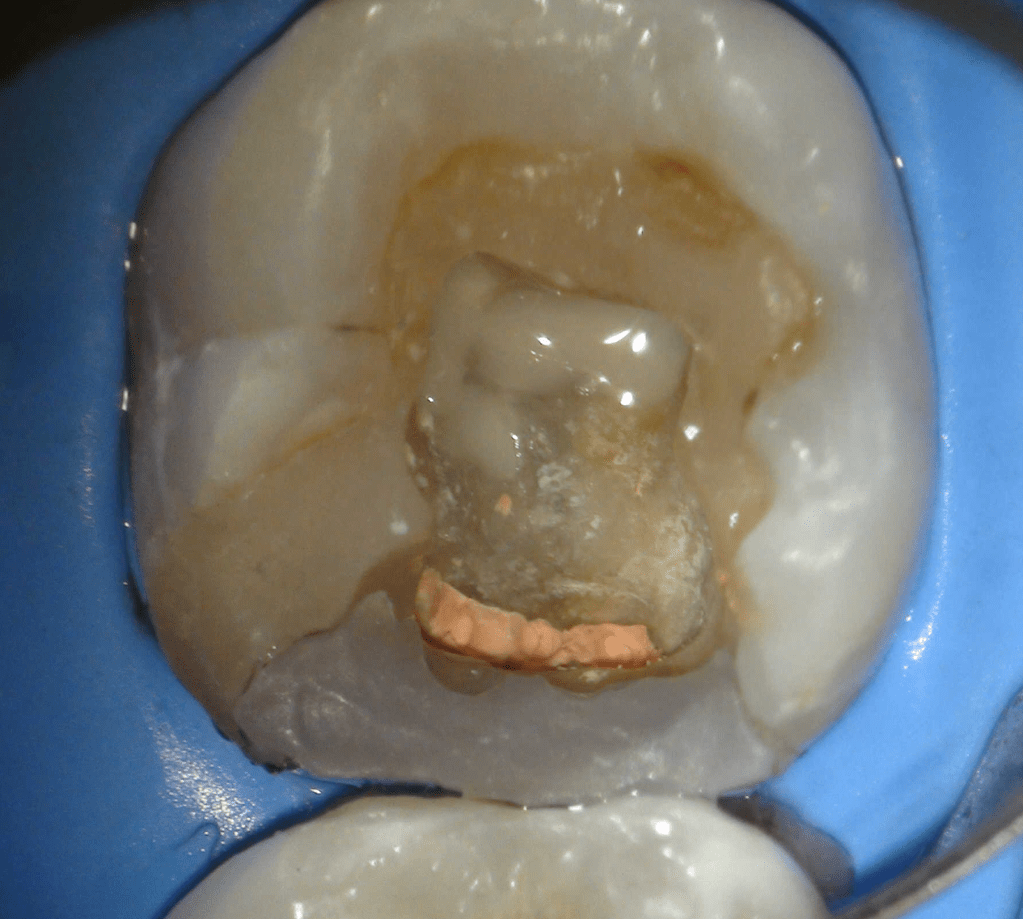

Reconstrucción preendodóntica

Reco pared vesticular

Reco pre-endo, molar inferior

Reco preendo + 4 conductos molar superior

Reco preendo, 2o Molar superior